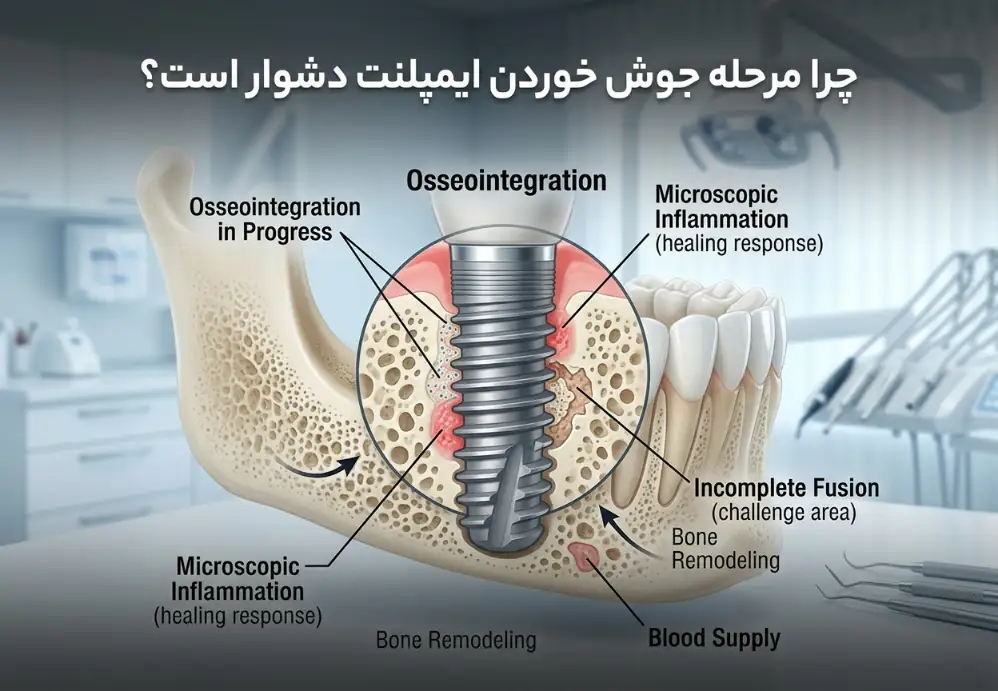

در میان مراحل مختلف ایمپلنت، بسیاری از متخصصان مرحله جوش خوردن ایمپلنت با استخوان فک را مهمترین و چالشبرانگیزترین مرحله میدانند. این فرآیند در دندانپزشکی با نام اُسیواینتگریشن (Osseointegration) شناخته میشود.

در این مرحله استخوان فک به تدریج اطراف پایه تیتانیومی ایمپلنت رشد میکند و آن را مانند یک ریشه طبیعی در خود نگه میدارد. این فرآیند نقش بسیار مهمی در موفقیت درمان دارد زیرا اگر ایمپلنت به درستی با استخوان فک جوش نخورد، ثبات لازم برای نگه داشتن دندان مصنوعی ایجاد نمیشود.

چرا مرحله جوش خوردن ایمپلنت دشوار است؟

مرحله اتصال ایمپلنت به استخوان فک دشوار محسوب میشود زیرا در این دوره بدن باید با ایمپلنت سازگار شود و استخوان جدید در اطراف آن تشکیل شود. این فرآیند یک واکنش طبیعی بدن است و زمان مشخصی برای انجام آن نیاز است.

در بسیاری از بیماران این مرحله حدود ۳ تا ۶ ماه طول میکشد و در این مدت استخوان فک به تدریج با سطح ایمپلنت پیوند میخورد و آن را محکم در جای خود نگه میدارد.

اگر در این مرحله فشار زیادی به ایمپلنت وارد شود یا مراقبتهای لازم انجام نشود، ممکن است فرآیند اتصال استخوان به ایمپلنت با مشکل مواجه شود.